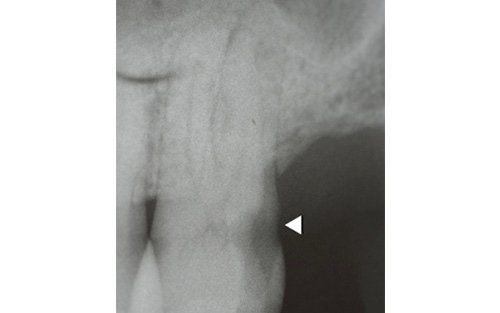

This treatment should be reserved for teeth that have irreversible pulp pathology (the nerve of the tooth) or an infection of the dental canals that has caused an abscess (acute apical periodontitis) or a granuloma (chronic apical periodontitis). While in the first two cases the tooth is very painful and the patient immediately seeks the dentist, the case of the chronic form is often silent, and therefore the patient may not notice anything for a medium to long period of time. In such conditions, it is only an X-ray image, taken during routine check-ups, that detects its presence. Root canal therapy can be completed by placing a latest-generation post inside the canal, as a means of retaining the material used for the reconstruction of the tooth. It will be up to the clinician to decide whether or not the restoration requires this additional anchoring system.